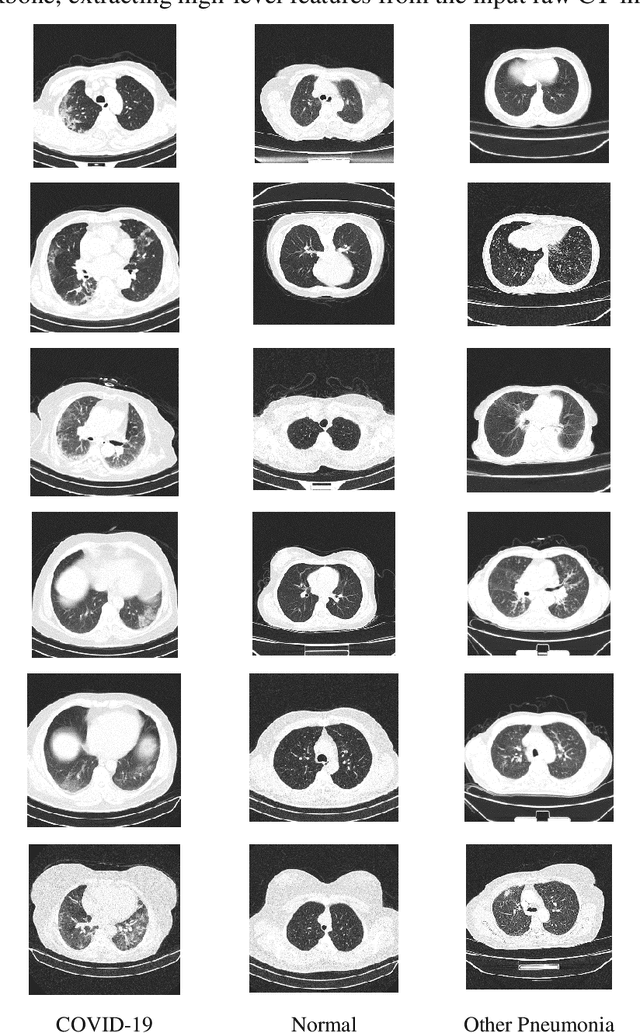

Abstract:The rapid outbreak of COVID-19 threatens humans life all around the world. Due to insufficient diagnostic infrastructures, developing an accurate, efficient, inexpensive, and quick diagnostic tool is of great importance. As chest radiography, such as chest X-ray (CXR) and CT computed tomography (CT), is a possible way for screening COVID-19, developing an automatic image classification tool is immensely helpful for detecting the patients with COVID-19. To date, researchers have proposed several different screening methods; however, none of them could achieve a reliable and highly sensitive performance yet. The main drawbacks of current methods are the lack of having enough training data, low generalization performance, and a high rate of false-positive detection. To tackle such limitations, this study firstly builds a large-size publicly available CT-scan dataset, consisting of more than 13k CT-images of more than 1000 individuals, in which 8k images are taken from 500 patients infected with COVID-19. Secondly, we propose a deep learning model for screening COVID-19 using our proposed CT dataset and report the baseline results. Finally, we extend the proposed CT model for screening COVID-19 from CXR images using a transfer learning approach. The experimental results show that the proposed CT and CXR methods achieve the AUC scores of 0.886 and 0.984 respectively.